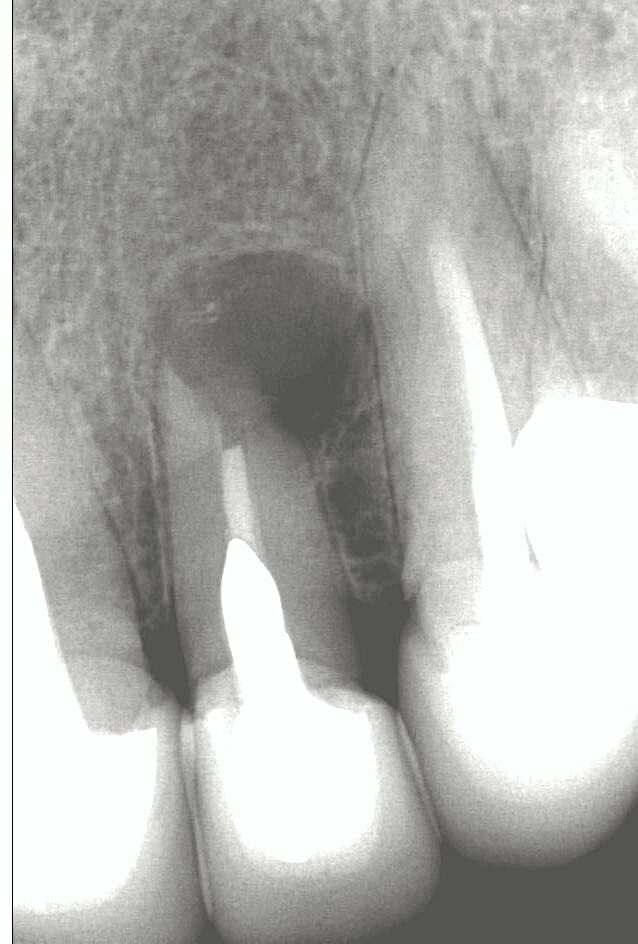

Sara (name changed to anonymise) attended my clinic with pain and infection in relation to a very heavily restored front tooth. Her dentist could no longer help her and advised that the tooth should be taken out.

She was worried about the consequences of losing her tooth and decided to seek advice from me to determine whether it was possible to treat this tooth again. We agreed to perform surgery to remove the infection and also encouraged healing by adding her own blood plasma to the bone space to help with healing. Seven months later, we were delighted to see the infection had cleared and bony healing occurring. The tooth was saved and is still going two years later!